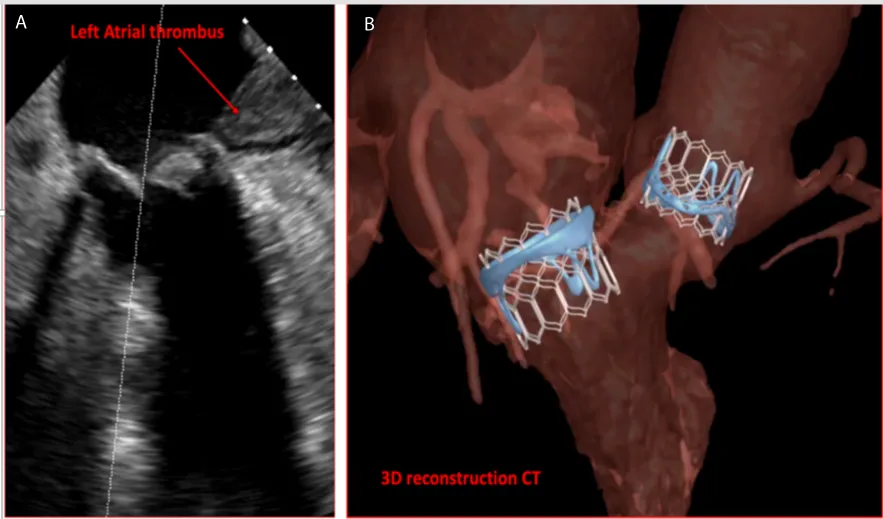

We report a 72 years old male patient case with past history of surgical aortic and mitral biological valves replacement with tricuspid ring in 2010. The patient presented severe dyspnea New York Heart Association (NYHA) class IV with stenotic aortic and mitral bio prostheses and left ventricle ejection fraction of 30%. The patient had no cardiovascular risk factor and received vitamin K antagonist (VKA) for persistent atrial fibrillation. Trans esophageal echocardiography (TEE) showed a severe aortic bioprosthesis stenosis with a mean aortic gradient of 32 mmHg, the estimated surface was 0.6 cm2 and a severe mitral bioprosthesis stenosis with a mean gradient of 20 mmHg, the estimated surface was 0.9 cm2 and pulmonary hypertension of 65 mmHg. TEE revealed the presence of a voluminous thrombus appended in the left atrium despite optimal anticoagulation (target INR stable between 2-3). The patient was screened for a double valves in valves procedure, coronary angiogram did not reveal significant coronary stenosis. We repeated the TEE after one month with the ad of aspirin on top of VKA to reduce the left atrial thrombus without success (Figure 1A). Heart team decision was to perform valves in valves (VIV) aortic and mitral replacement via transapical access due to the contra indication to use the transeptal access for the mitral bioprosthesis VIV. We planned this procedure with cardiac computed tomography (CT), 3-dimension reconstruction and VIV implantation simulation (Figure 1B). To rule out the high risk of stroke emboly during the procedure we involved interventional neurologist to perform cerebral angiography just after VIV implantations. The procedure was performed under general anesthesia with arterial femoral access 6F and venous femoral access 7F to introduce a temporary pacemaker. The transapical access was complicated with right ventricle laceration an urgent peripheral arteriovenous extracorporeal membrane oxygenation (ECMO) was implanted to unload the right ventricle and perform the hemostasis with success. Thereafter, we performed first a VIV implantation with an Edwards Sapien n°3 26 mm in aortic position and VIV implantation with an Edwards Sapien n°3 29 mm in mitral position without complication (Figure 2). Cerebral angiography did not showed occlusion of main cerebral arteries. ECMO was removed the same day and patient was discharged at home after 14 days relief of symptoms and without adverse neurological outcome. At 6 months follow up, patient was asymptomatic with stable mean gradients of 11 mmHg for the aortic VIV and 7 mmHg for the mitral VIV, left ventricle ejection fraction was 45%. Controlled CT showed thrombus regression and 3-dimension reconstruction was similar to the simulation.

Figure 2: VIV procedure A: Trans aortic VIV positioning B: Tran’s aortic VIV deployment C: Trans mitral VIV positioning D: Tran’s mitral VIV deployment